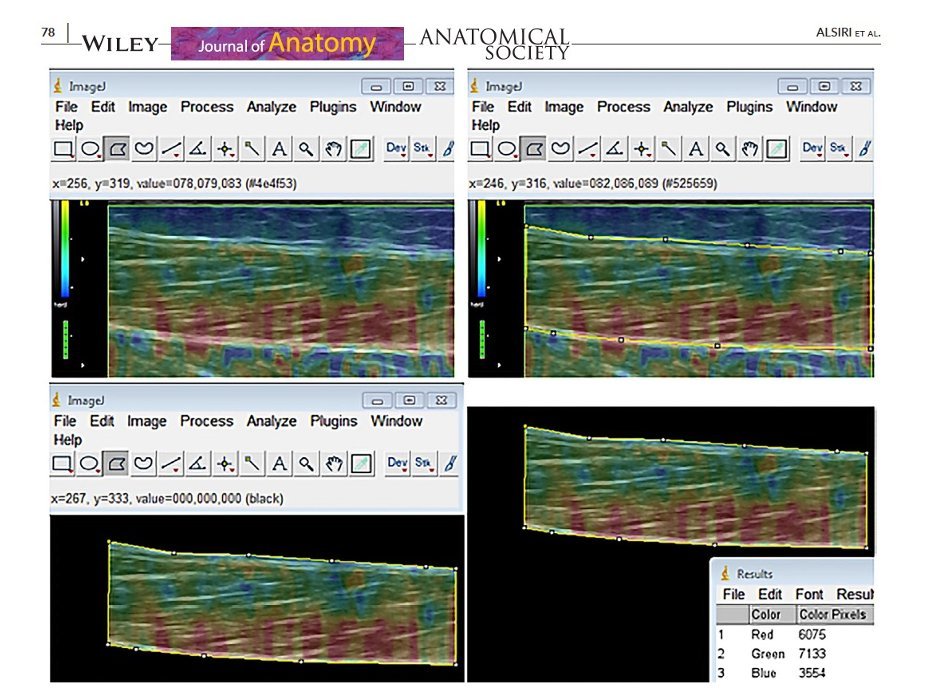

Dr. Najla Alsiri is a pioneering figure in the field of musculoskeletal and quantitative research practice, being one of the first individuals to introduce sonoelastography technology into this domain. Originally designed for oncology, this innovative system assesses the elasticity of musculoskeletal structures, offering significant value for clinical examinations, diagnoses, and management, as well as serving research purposes. Dr. Alsiri’s impactful journey began with a series of publications from 2016 to the present in Q1 journals, starting with the assessment of the system’s feasibility, followed by establishing its reliability and smallest detectable change.

The research then progressed to differentiate between healthy tissues and those affected by connective tissue disorders.